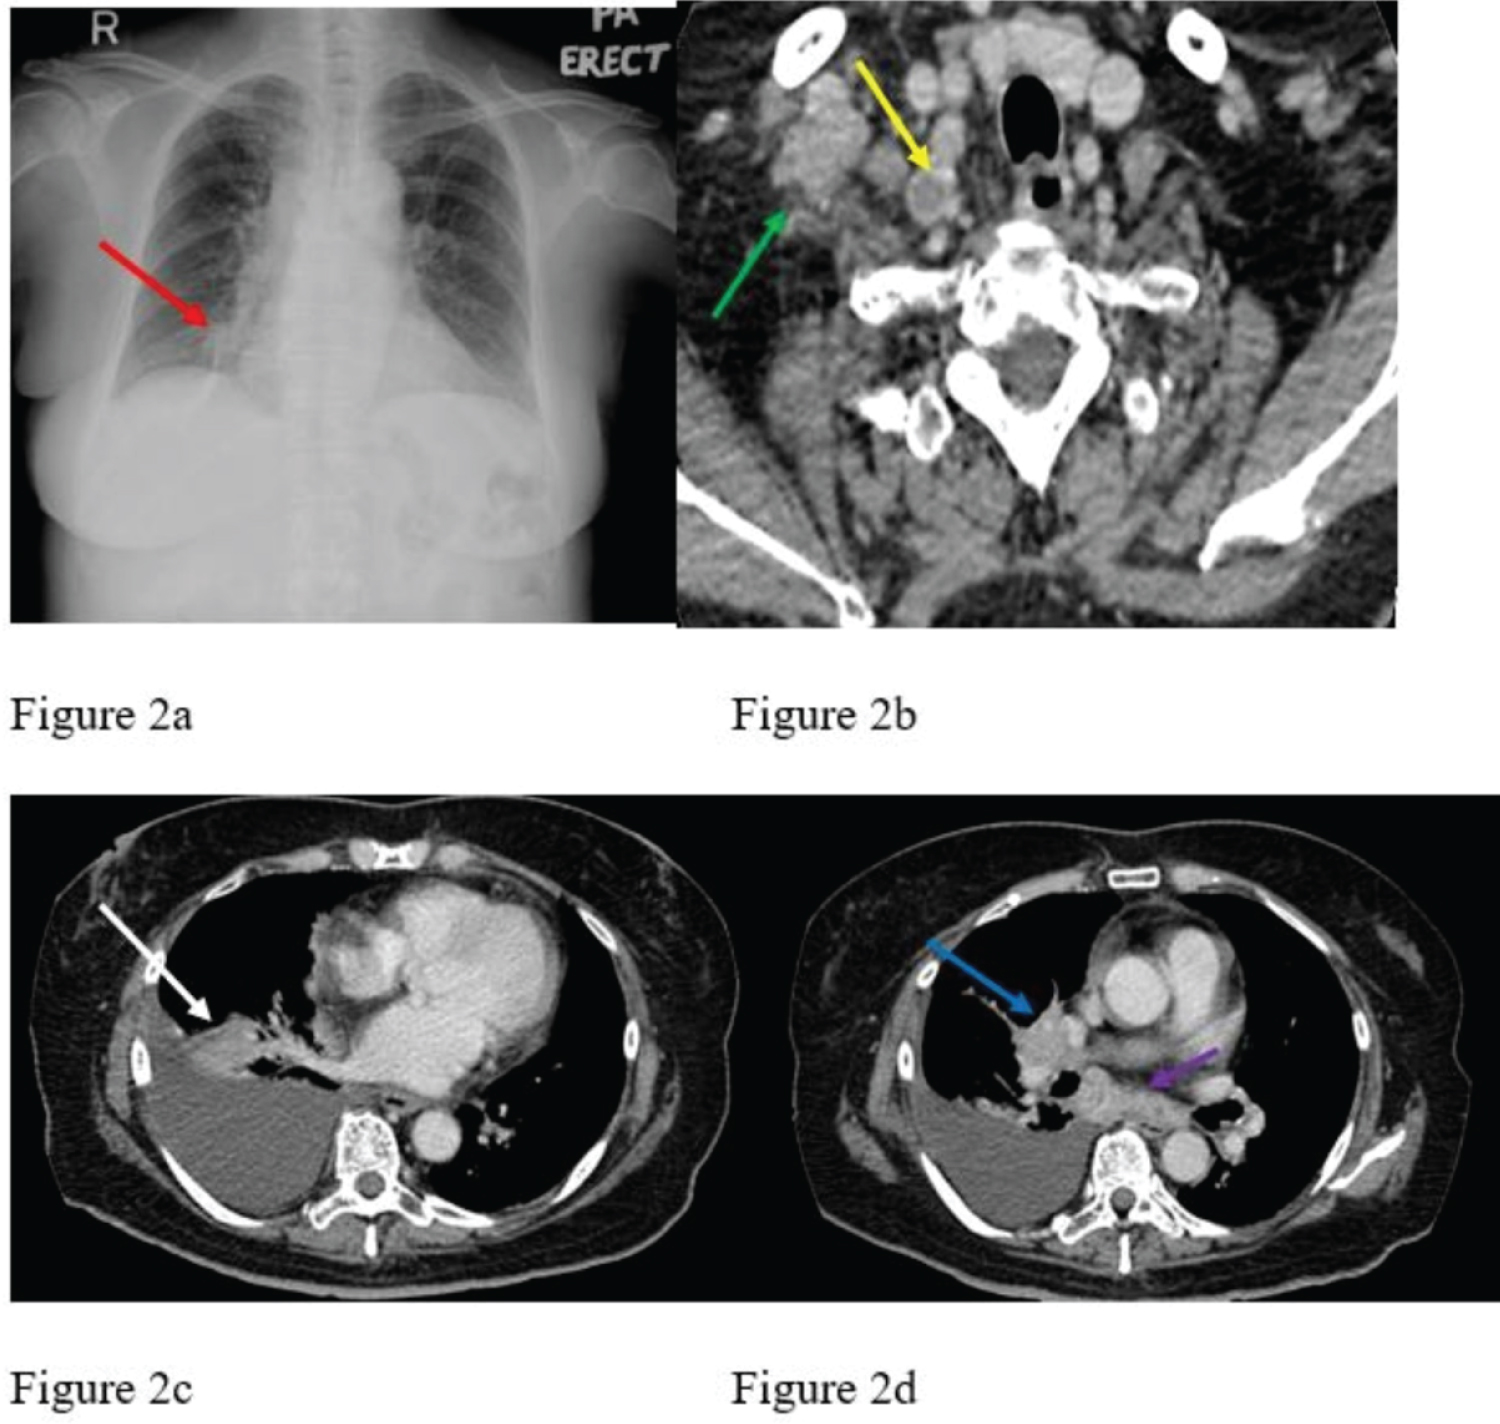

Laboratory results revealed a total white cell count of 11.8 × 10^3/uL and platelet count of 458 × 10^3/uL. The absolute eosinophil count of 300 cells per microliter was normal. Erythrocyte sedimentation rate (ESR) was raised at 41 mm/hr. Liver and renal function tests were unremarkable. Immunological workup was positive for anti-Ro-52 antibodies and antinuclear antibodies (ANA) at a titer of 1:1280 (nucleolar pattern). Anti-centromere and anti-topoisomerase I were negative, while Anti-RNA polymerase III was not available at our center. Musculoskeletal ultrasound demonstrated active synovitis with corresponding doppler activity (grade 3 synovitis and grade 3 doppler) and tenosynovitis of her right first to third MCPJ, left first to second MCPJ, and all the PIPJ of both hands. Capillaroscopy was not performed. Transthoracic echocardiography revealed no evidence of pulmonary hypertension. A chest radiography performed for the lungs auscultatory findings revealed a suspicious right lower lobe nodule (Figure 2a). Follow-up contrast-enhanced computed tomography of the thorax demonstrated a right lower lobe ill-defined heterogeneously enhancing lung mass measuring 2.2 × 4.6 × 2.4 cm with mediastinal and right supraclavicular lymphadenopathy (Figure 2b, Figure 2c and Figure 2d) as well as right pleural effusion. Right supraclavicular lymph node incisional biopsy was performed, and the histopathological examination revealed metastatic adenocarcinoma with immunohistochemistry studies suggesting a lung primary tumor (positive for CK7 and TTF-1, negative for CK20 and p40). Further testing for EGFR mutation and ALK was negative.

Figure 2: Initial chest radiograph (Figure 2a) revealed a suspicious right lower zone lung nodule (red arrow) adjacent to the right heart border. Subsequent contrast-enhanced computed tomography of the thorax confirmed the finding of a right lower lobe enhancing lung mass (white arrow in Figure 2c) as well as right pleural effusion with associated right hilar (blue arrow) as well as subcarinal lymphadenopathies (purple arrow) in Figure 2d. The image at the upper thoracic level (Figure 2b) also showed enlarged right supraclavicular lymph nodes, some with necrotic centers (green and yellow arrows). View Figure 2